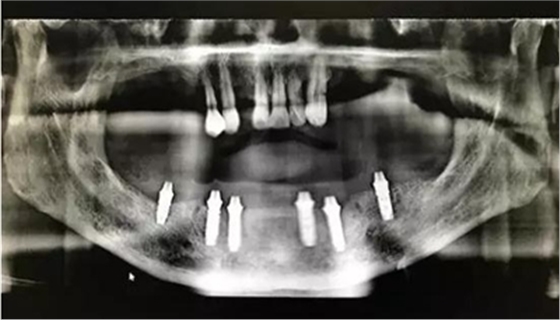

通過術(shù)前精確的設(shè)計(jì),避開了患者骨壁較薄需要做骨劈開的區(qū)域,避免了大翻瓣造成較大創(chuàng)傷,大大提高了患者的舒適度。

全程手術(shù)采用小翻瓣微創(chuàng)種植,選擇初期穩(wěn)定性較好的植體進(jìn)行即刻負(fù)重。整個(gè)手術(shù)從開始到最終戴上臨時(shí)牙,只花費(fèi)2個(gè)小時(shí)的時(shí)間,就讓患者恢復(fù)了完美笑容。數(shù)字化種植為醫(yī)生和患者帶來不一樣的感受!